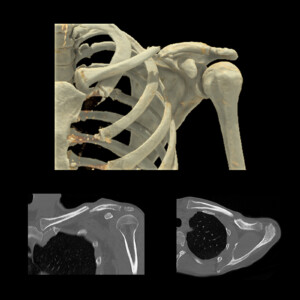

Χρησιμοποιείται για την απεικόνιση αστικών αλλοιώσεων, κηλών μεσοσπονδυλίων δίσκων, καταγμάτων κυρίως σε ασθενείς που δεν μπορούν να υποβληθούν σε μαγνητική τομογραφία μυοσκελετικού συστήματος.